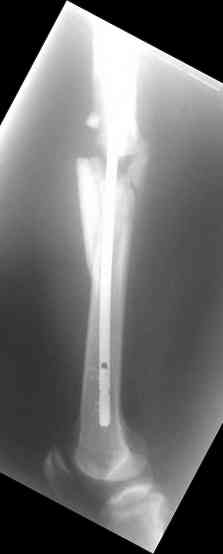

молодй человек 26лет получил С3-перелом правого бедра и легкую черепно мозговую травму (сотрясение головного мозга). Через неделю (противошоковые мереприятия и скелетное вытяжение выполнялось в ЦРБ)оперирован: БИОС бедра стержнем СнМ, Польша. Выписан со швами на амбулаторное лечение по месту жительства в г. Ижевск.Через 1месяц главным врачом больницы, со слов пациента, предложен реостеосинтез пластиной "соберем кость".

Надеюсь сейчас показать перелом, а потом синтез.

У данного пациента есть все основания ожидать несращения. Менять штифт (безусловно тонкий и недостаточно стабильный для этого перелома) на пластину не лучший вариант, особенно, если предполагается открытая операция. Или главный врач в Ижевске имеет ввиду длинную мостовидную пластину LCP по технике MIPO? Тогда шансов на сращение будет больше, чем сейчас, но с нагрузкой придется очень и очень подождать.

Мы бы сейчас перештифтовали : удалить, рассверлить, и забить штифт 13-16 мм диаметром и на пару см. подлиннее. Предпочтительнее штифт, имеющий изгиб во фронтальной плоскости в проксимальном отделе для введения через верхушку б\вертела и имеюший возможность проксимального блокирования по оси шейки бедра.